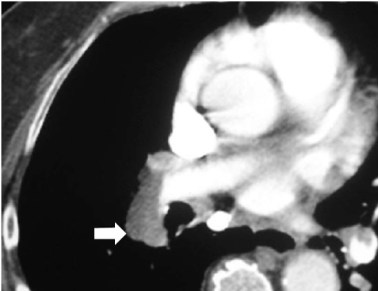

SIGNO DE FLEISHNER o DEL HILIO ABULTADO o DEL NUDILLO

En la radiografía posteroanterior o anteroposterior de tórax, la presencia de una arteria pulmonar agrandada puede indicar tromboembolismo, especialmente cuando no está presente en los estudios previos. Este signo también se llama signo de plump hilus o Signo del nudillo.

En el corte del angioTC de tórax con contraste del mismo paciente, vemos un aumento de tamaño de la arteria pulmonar, que presenta un defecto de repleción (flecha) correspondiente al tromboembolismo.